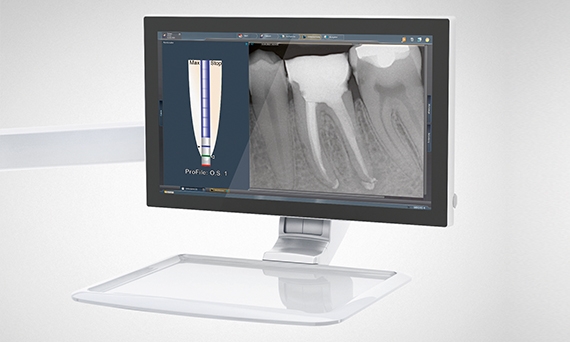

In today's world, "digital" is omnipresent, and has long since arrived in the dental industry. At Dentsply Sirona, we are constantly developing digital solutions - not for the sake of being innovative, but for the benefit of you and your patients. A digitally connected treatment center is dedicated towards supporting your workflows. It streamlines processes, since functions for patient communication, implant or endo treatments are already integrated. It provides you and your patients with all relevant information needed during a treatment.